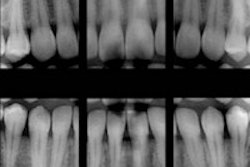

Digital imaging and rectangular collimation should be used to ensure that the ALARA (as low as reasonably achievable) principle can be maximized when taking bitewing radiographs in pediatric patients, according to a poster presentation at the American Academy of Oral and Maxillofacial Radiology (AAOMR) annual meeting last month.

An epidemiological study published earlier this year in the journal Cancer prompted a flurry of media coverage and public concern because it claimed to have found a link between frequent bitewing x-ray exposure and increased risk of developing meningioma.

Dr. Branets and colleagues from NYU College of Dentistry, Stony Brook University School of Dental Medicine, and Memorial Sloan-Kettering Cancer Center used two anthropomorphic CIRS juvenile phantoms (5 years old and 10 years old) to gather dosimetric measurements on the x-ray exposures from bitewing radiographs using round and rectangular collimation for both film and digital radiography.